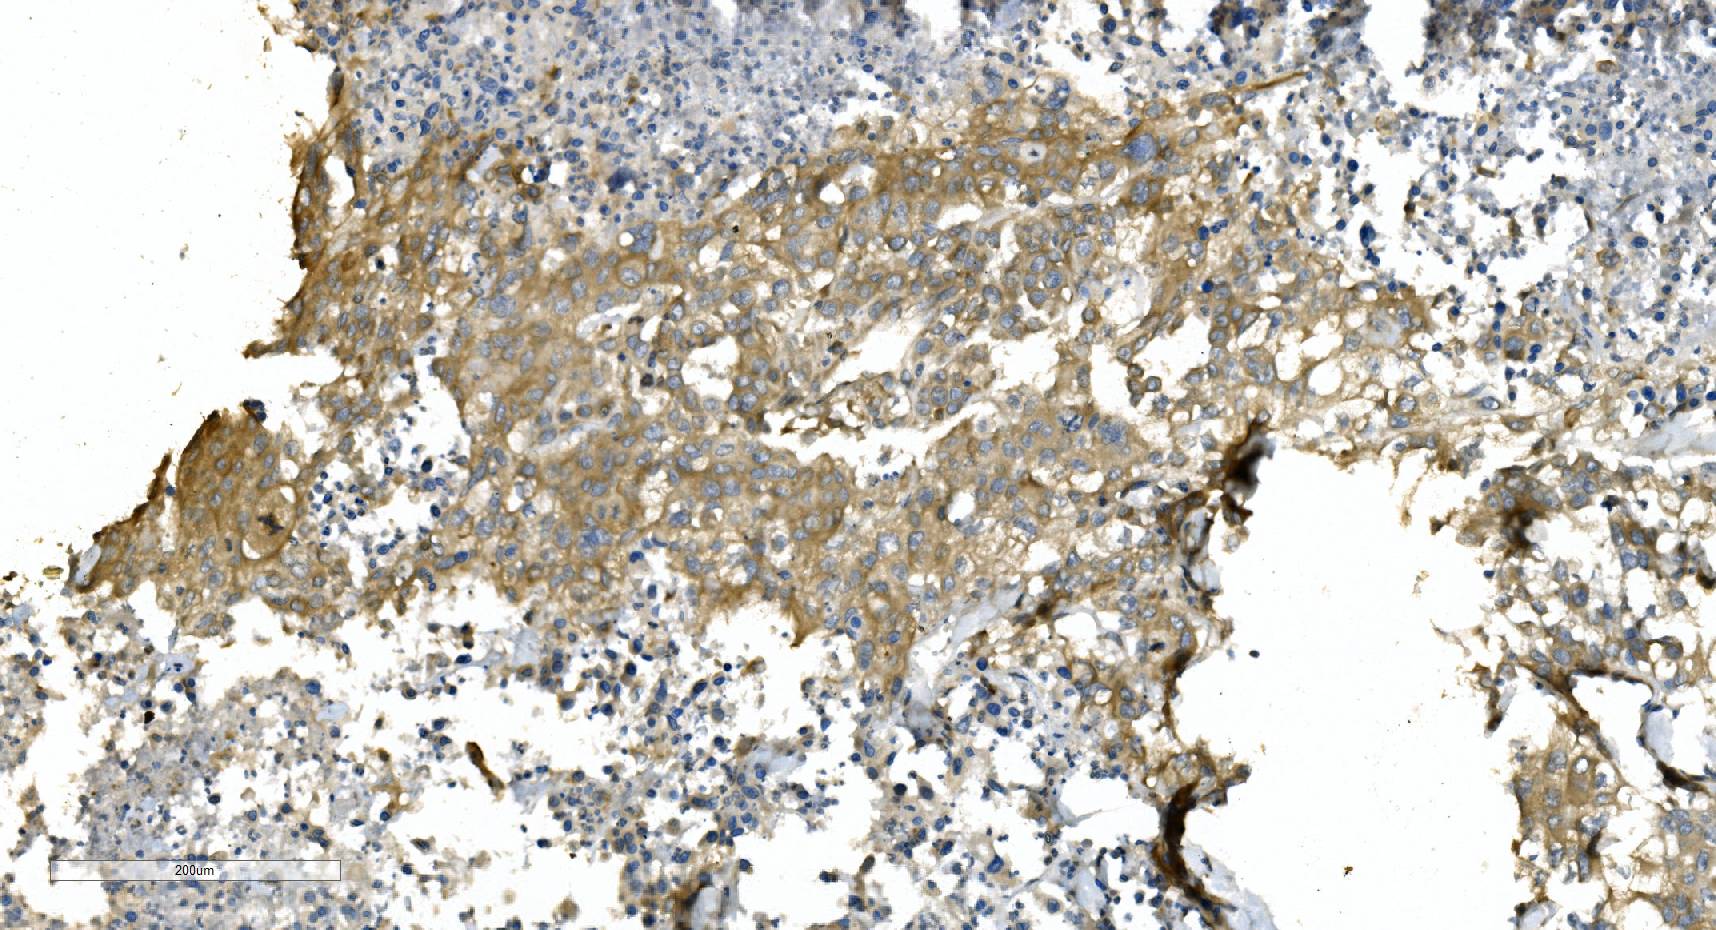

IHC analysis of Alpha Tubulin/TUBA1A using anti-Alpha Tubulin/TUBA1A antibody (M03989-3).

Alpha Tubulin/TUBA1A was detected in a paraffin-embedded section of human breast cancer tissue. Biotinylated goat anti-mouse IgG was used as secondary antibody. The tissue section was incubated with mouse anti-Alpha Tubulin/TUBA1A Antibody (M03989-3) at a dilution of 1:200 and developed using Strepavidin-Biotin-Complex (SABC) (Catalog # SA1021) with DAB (Catalog # AR1027) as the chromogen.